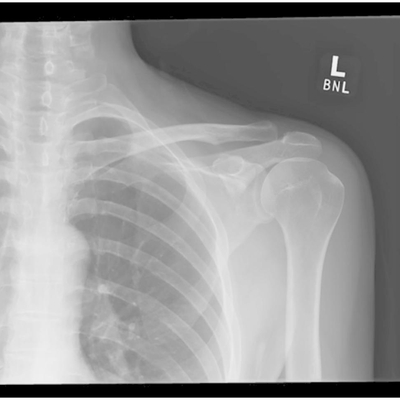

Click on an image below to view more info.